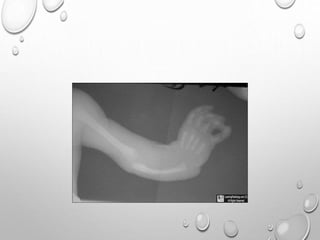

DIASTROPHIC DYSPLASIA

A TYPE OF SHORT LIMB SKELETAL DYSPLASIA

RELATIVELY INCREASED PREVALENCE IN FINLAND

RADIOLOGY :

MICROMELIA – RHIZOMELIC TYPE

HITCH HIKER THUMB

MULIPLE POSTURAL DEFORMITY , JOINT CONTRACTURE

KYPHOSCOLIOSIS

LONG BONES – RHIZOMELIC SHORTENING

CRESCENT SHAPED FLATTENED EPIPHYSES

CLUB FOOT

CAULIFLOWER EAR

DOUBLE LAYERED MANUBRIUM ....SPECIFIC FOR IT